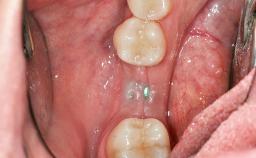

Soft-Tissue Volume Augmentation Using a Connective-Tissue Graft Harvested from the Maxillary Tuberosity

In 1983, a 51-year-old non-smoking patient was referred for the treatment of moderate chronic periodontitis. At the initial examination, 47% of sites exhibited probing depths of 4 to 6 mm. Periodontal therapy consisted of initial periodontal treatment including oral-hygiene instructions and supra- and subgingival debridement, followed by periodontal surgery to eliminate residual pockets.